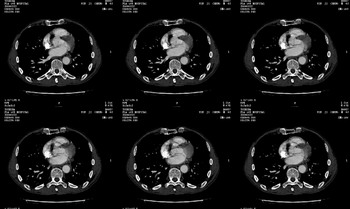

男 62 夜间突然腹痛并向背部放射 ,急诊疑胰腺炎 ,胰淀粉酶正常 ,ct示胰腺未见明显异常,发现降主动脉密度欠均,做主动脉造影示胸腹主动脉半月形低密度充盈缺损,内膜钙化并内移,累及腹腔干致根部明显狭窄,未见明显破裂口。 本人为是不典型夹层,其他人有说是动脉硬化或动脉炎的。请大家发表一下看法。

可惜图像太小,但结合病人年龄、病史及降主动脉壁增厚及模糊表现应该考虑,在我看到的急性主动脉夹层别人中血管壁都有这样改变。